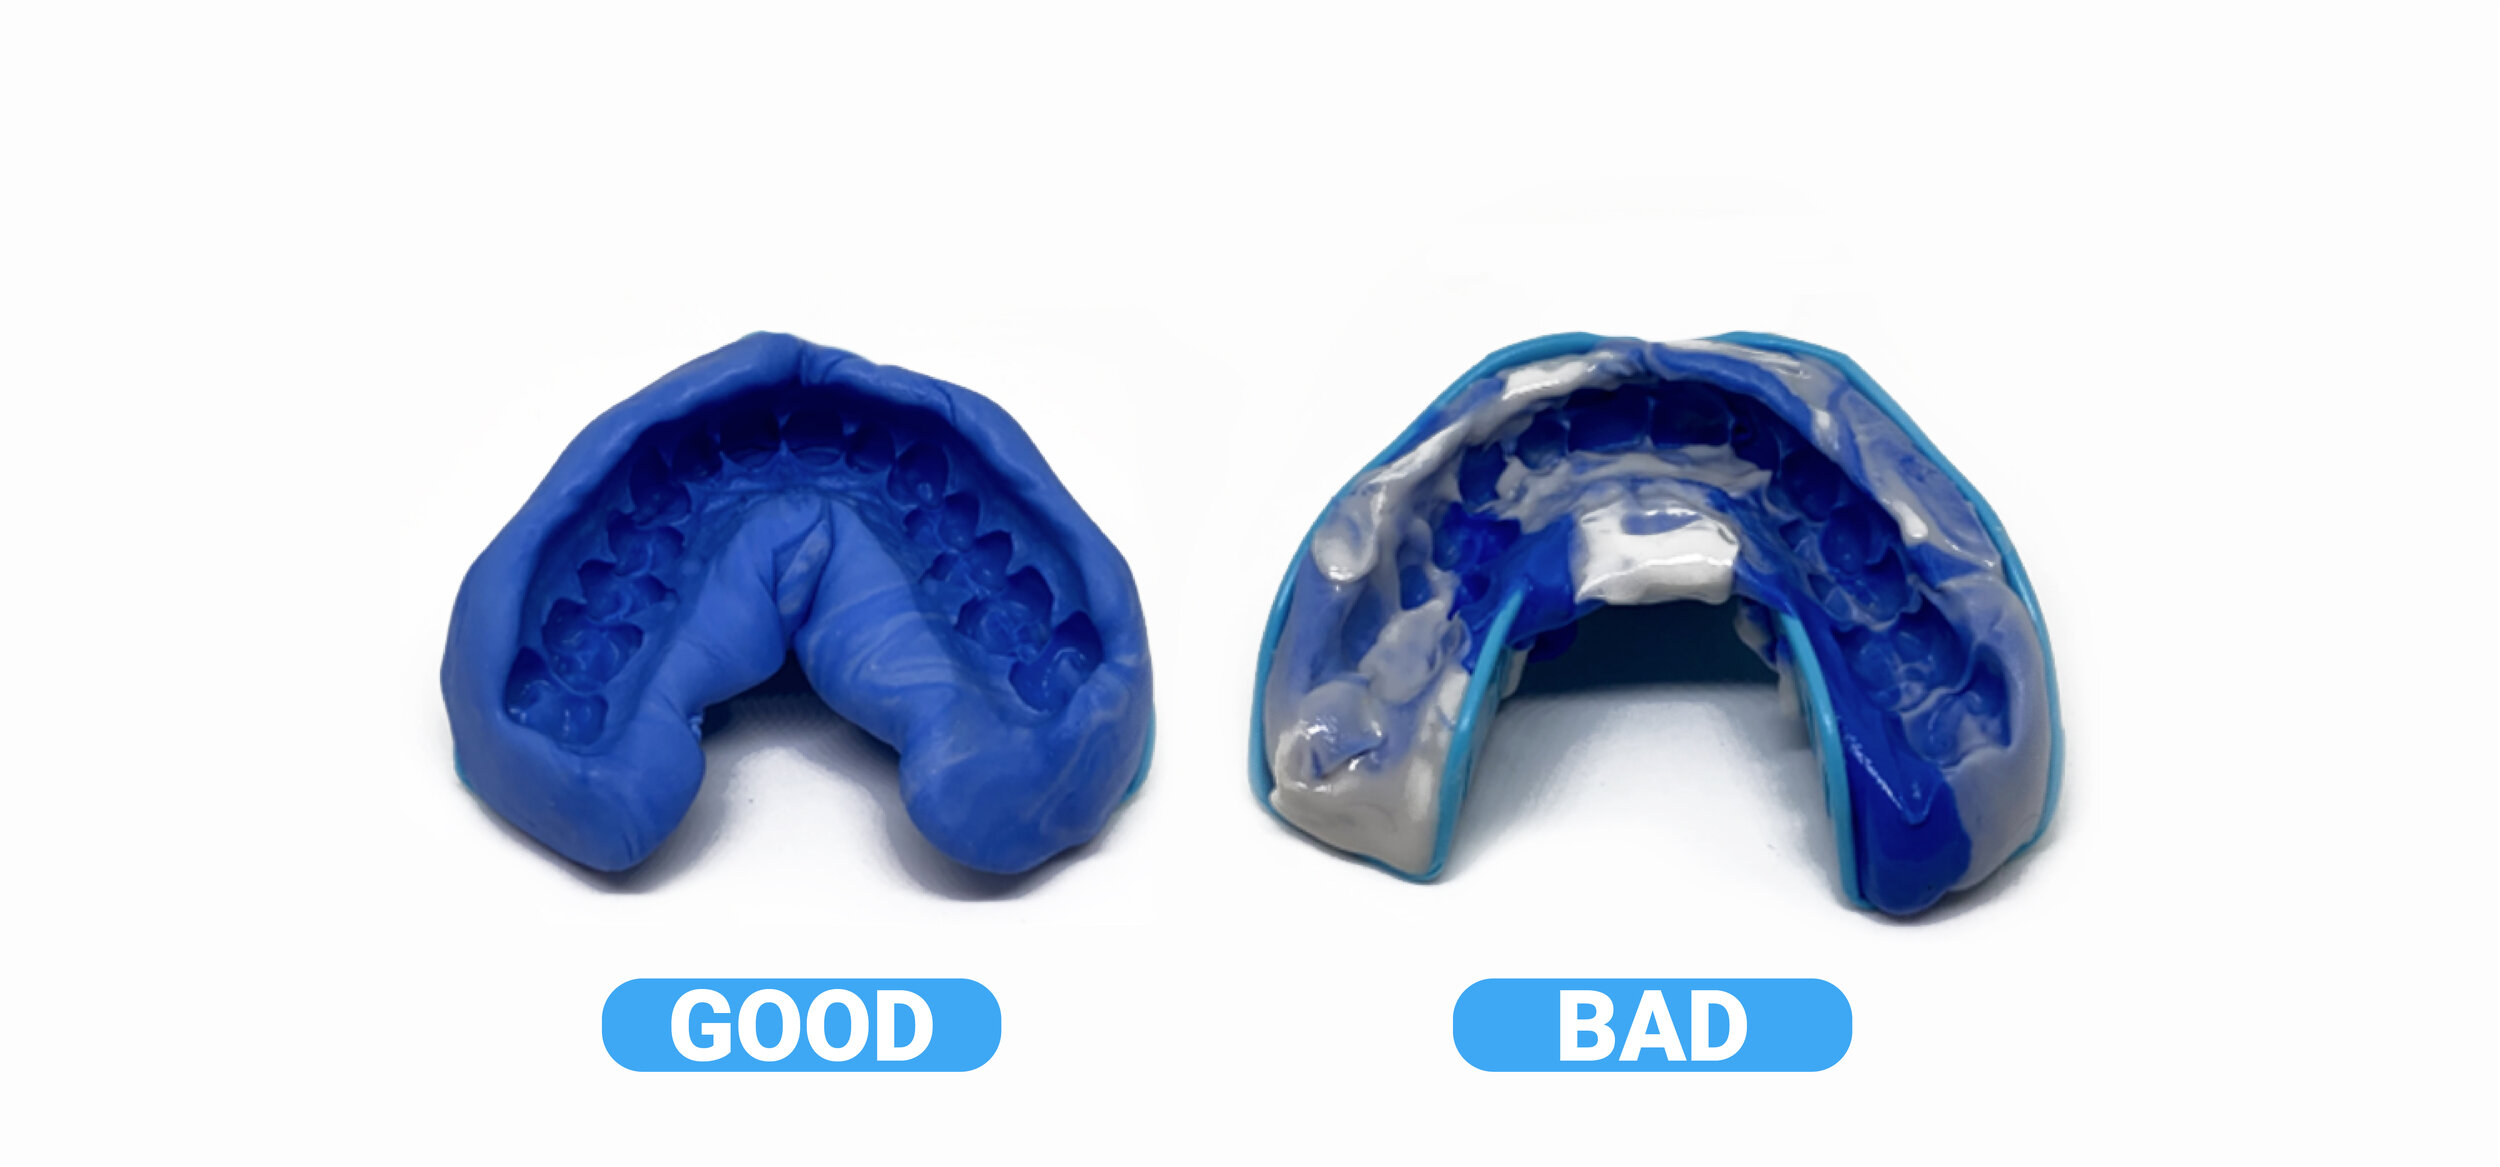

Taking Impressions

Taking Impressions

Taking Impressions

Taking Impressions

Taking Impressions

Taking Impressions

Taking Impressions

Taking Impressions

Taking Impressions

Taking Impressions

Taking Impressions

Taking Impressions

Taking Impressions

Taking Impressions

Taking Impressions

Taking Impressions

Taking Impressions

Taking Impressions

Text

Taking Impressions

Text

Taking Impressions

Taking Impressions